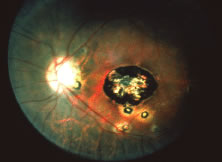

Progression of the retinitis generally occurs with a leading edge of active retinitis and a trailing region of thin gliotic retina. This pattern indicates cell to cell transmission of the virus. CMV is a slowly progressive, necrotizing retinitis that may affect the posterior pole, the peripheral retina, or both and may be unilateral or bilateral. Involved areas appear as white intraretinal lesions; areas of infiltrate; and often necrosis, along the vascular arcades in the posterior pole. In addition, prominent retinal hemorrhages are often seen within the necrotic area or along its leading edge (Figs. 12 and 13). Peripherally, CMV retinitis tends to have a less intense white appearance, with areas of granular, white retinitis that may or may not demonstrate associated retinal hemorrhage (Fig. 14). As the retinitis progresses, an area of atrophic, avascular retina may remain with underlying retinal pigment epithelial atrophy and/or hyperplasia (Fig. 15).57,58,60,62 Peripheral CMV retinitis may be the most common form of CMV retinitis seen. Patients may initially complain only of floaters with or without a visual field deficit.57 Wide-angle fundus photography and fluorescein angiography may be of benefit when the diagnosis is uncertain. These techniques may be used to document progression of retinitis, and fluorescein leakage in areas of retinitis may be helpful in confirming the diagnosis. Although peripheral CMV retinitis may not pose an immediate threat to vision, initiation of treatment should be seriously considered because several investigators have shown that untreated CMV retinitis is inexorably progressive and becomes bilateral in virtually all untreated patients.59,60,65,74–76 Occasionally, noncontiguous areas of new retinitis may be seen. As healing takes place, a thin glial scar replaces the necrotic retinal tissue. The transition from infected to noninfected retina is usually sharply demarcated and well seen during the active phase of the disease. When healing takes place, the transition zone is between a glial scar and normal retina and may be difficult to visualize. Clinically, the pigment epithelium tends to develop a characteristic spiculated granular appearance directly under the residual glial scar. The retina in the immediately adjacent uninvolved areas is thick in comparison to the glial scar, thus, differing light reflexes occur with indirect ophthalmoscopy. Using the pigment epithelium pigment changes and light reflexes, one can define the extent of prior retinal involvement. More importantly, defining the edge of prior involvement allows one to predict with great accuracy the sites of new involvement, allowing for more effective monitoring of therapeutic efforts to control the infection. Other manifestations of CMV retinitis include retinal edema, attenuated vessels, perivascular sheathing, and exudative retinal detachment.77 In addition, vitreitis and anterior uveitis are often seen,70 and optic atrophy may occur as a late manifestation secondary to widespread retinal destruction. CMV may be demonstrated in vitreous biopsy specimens in these patients.65 The yield may be higher in the presence of marked vitreitis because CMV is a cell-associated virus. Other causes of retinitis, including herpes simplex retinitis,78,79 toxoplasmosis,80 Candida, Behçet's disease, syphilis, ARN,7,28,81 and SSPE82 can usually be distinguished from CMV on clinical grounds. Cotton-wool spots are nonspecific and may be seen in diabetes mellitus, hypertension, severe anemia, systemic lupus erythematosus, dermatomyositis, and leukemia,83,84 as well as AIDS. It may be difficult to distinguish a small focus of nonhemorrhagic CMV retinitis from a cotton-wool spot corresponding to the area of peripapillary optic nerve fiber layer that was destroyed (Figs. 16 and 17). In eyes in which CMV infection initially involves the optic nerve head, the visual acuity may be normal early; however, the visual prognosis may be poor because these eyes often go on to loss of light perception (see Fig. 13). When retinitis is in close proximity to the optic nerve head or macula, a serous retinal detachment may be seen that will resolve with therapy.

Fig. 12. A patient with a relatively nonhemorrhagic variant of cytomegalovirus retinitis. Note at the center of the lesion (oldest area of infection) the retina is atrophic and pigmentary changes can be seen. Peripheral to it the retina is edematous, and this is the area of active infection.

Fig. 13. A patient with hemorrhagic variant of cytomegalovirus (CMV) retinitis that affected the posterior pole and optic nerve. Hemorrhages are most often intraretinal, and white areas correspond histologically to intracellular and extracellular edema and necrosis of the neurosensory retina. Eyes with extensive optic nerve involvement secondary to retinal involvement may still retain good central vision unless the papillomacular bundle is involved. When retinitis starts in the optic nerve head, the prognosis for vision is poor.